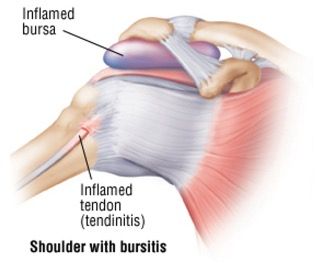

What is Bursitis?

A bursa is a sac that is filled with lubricating fluid that acts as a cushion. They are located between tendons and bones, tendons and ligaments or other areas where friction occurs. A bursa is designed to reduce the friction, rubbing and irritation in the area to allow a joint and its associated muscles and ligaments to move freely. Bursae are located in many regions of the body. Common areas where we see problems in the bursa are the shoulder and the hips.

Bursitis is when the bursa becomes inflamed. This can occur for several different reasons including trauma to the area and incorrect biomechanics in the area, causing change of load and change of movement to the muscles and joints in the area. Repetitive use and/or loading of a joint can also be involved in developing bursitis.

When a bursa becomes inflamed, it will fill with excess fluid. This can result in localised swelling, stiffness of the joint with restriction in movement and localised pain in the area. The pain can be described as a sharp pain or constant dull pain. The pain can be worse at night and is often worse with the movement of the involved joint.

The diagnosis of a bursa involves a history of the symptoms and a physical examination of the area. This may be followed by an X-ray to rule out any other condition and Ultrasound.

Treatment of a bursa involves resting the area and reducing the activity which caused the bursitis, ice to the area to reduce the inflammation and gentle mobilising exercises. As Chiropractors, we work with the biomechanics in the area to ensure that they are functioning correctly. By improving the biomechanics to the involved joint we aim to reduce the inflammation and help with the improvement of the inflamed bursa.

A lot of bursitis that is seen is due to repetitive strain to a joint that has occurred over an extended period. The treatment of bursitis takes time, combined with modification of the causative factors.